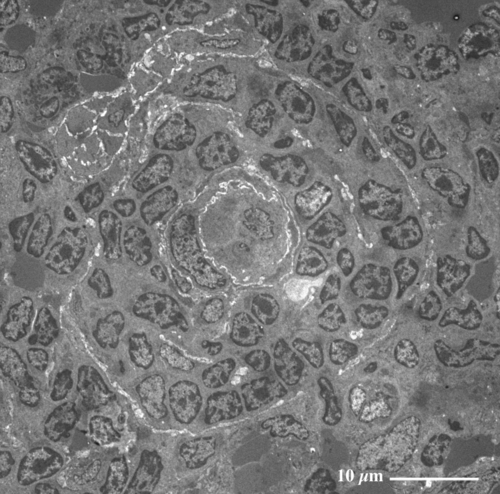

脾 臓(ラット) Spleen ( rat )

厚さ1 µm エポン樹脂準超薄切片のトルイジンブルー染色光学顕微鏡画像

Light microscopic image of 1 µm-semithin epoxy resin section with toluidin-blue staining

脾臓は最大のリンパ器官で、免疫機能や老朽化した赤血球の処理などに働く。

(エポン樹脂包埋準超薄切片のトルイジンブルー染色光顕像)